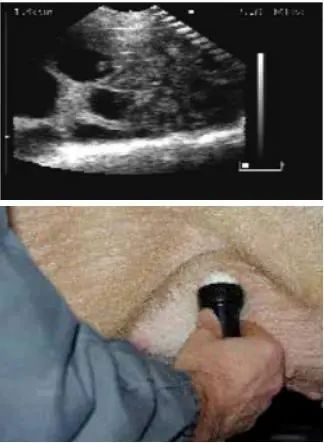

2.4 不同位置的扫描影像图

用B超进行妊娠鉴定时,应检测母猪身体的不同部位,以获得子宫内的详细情况,不同位置的扫描影像见图1、图2、图3、图4和图5。

图 2 位置2超声波影像图